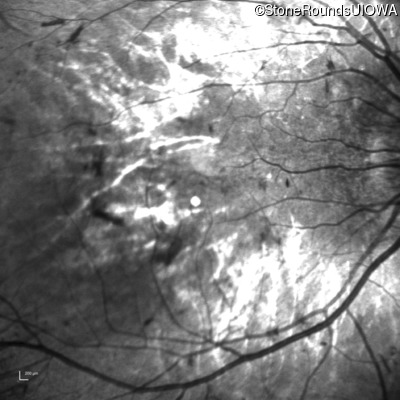

This 12 year old girl has had poor night vision and subnormal acuity since she was about 3 years old.

| Age at visit: 12 years (Visit 2) |